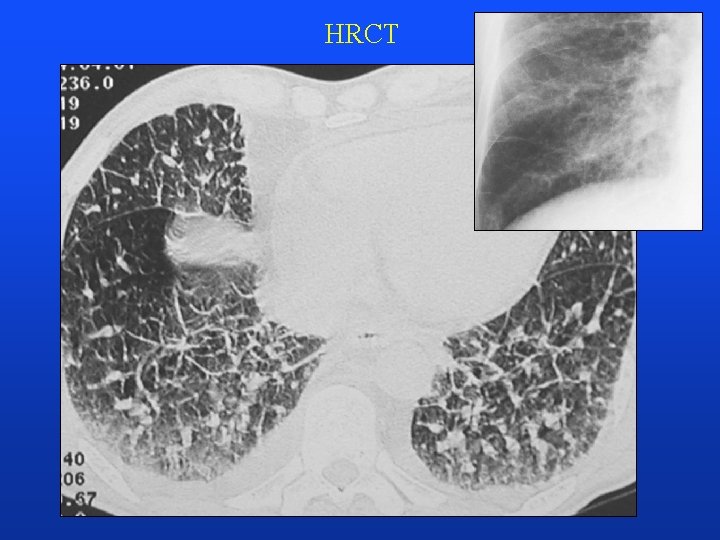

HRCT

Advances in CT • spiral (helical) CT • - volumetric imaging • no gaps due to breathing • faster scanning, CTA feasibility • multidetector systems • HRCT - (lung, bones – petrous bone etc) • thin collimation of sections • high resolution image recostruction algorithm